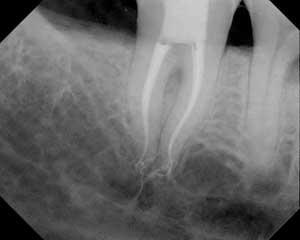

One of the most challenging nonsurgical anatomic entities that a clinician must address is rapidly curving apical anatomy. Canals that are relatively straight in the coronal half of the roots that abruptly curve in the apical half are at risk for ledging, blockage, instrument separation, and transportation of the minor constriction of the apical foramen, among a host of other possible iatrogenic events. Such a tooth is shown in Fig. 1.

It is noteworthy that the treatment shown was performed with .10 and .08 Twisted Files (SybronEndo). Because TF is never ground across its crystalline grain structure due to its fracture resistance and flexibility, it is able to be inserted into apical curvatures in tapers that were not previously possible. TF is used crown down, from larger to smaller tapers with the aforementioned irrigation, recapitulation, and insertion sequence. I welcome your questions and feedback.